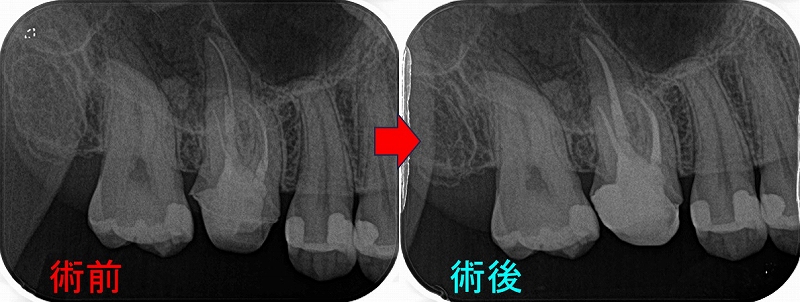

・外科的歯内療法:7本(前歯:2本 小臼歯:2本 大臼歯:3本)

根管治療で治らない歯を対象としています。最初から外科的歯内療法をチョイスすることは稀です。